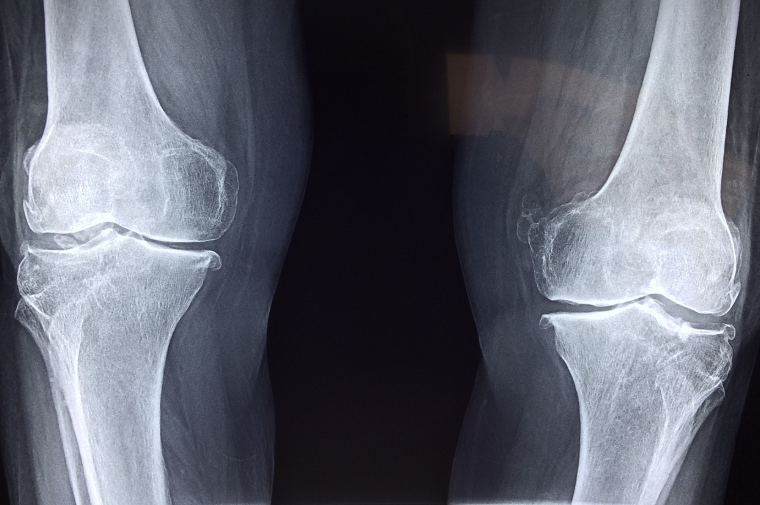

무릎 관절염은 고령층에서 흔히 발생하는 질환 중 하나로, 일상생활에 큰 불편을 초래합니다.

- 무릎관절증(퇴행성 관절염)으로 인해 지속적인 통증에 시달리는 노인의 고통 경감